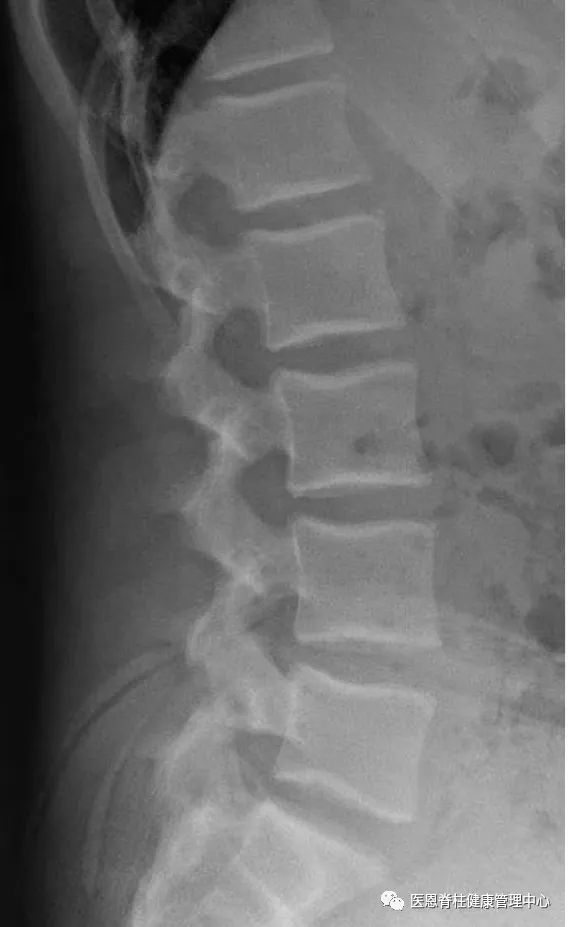

图:腰椎的生理曲度跟颈椎类似,也凸向前